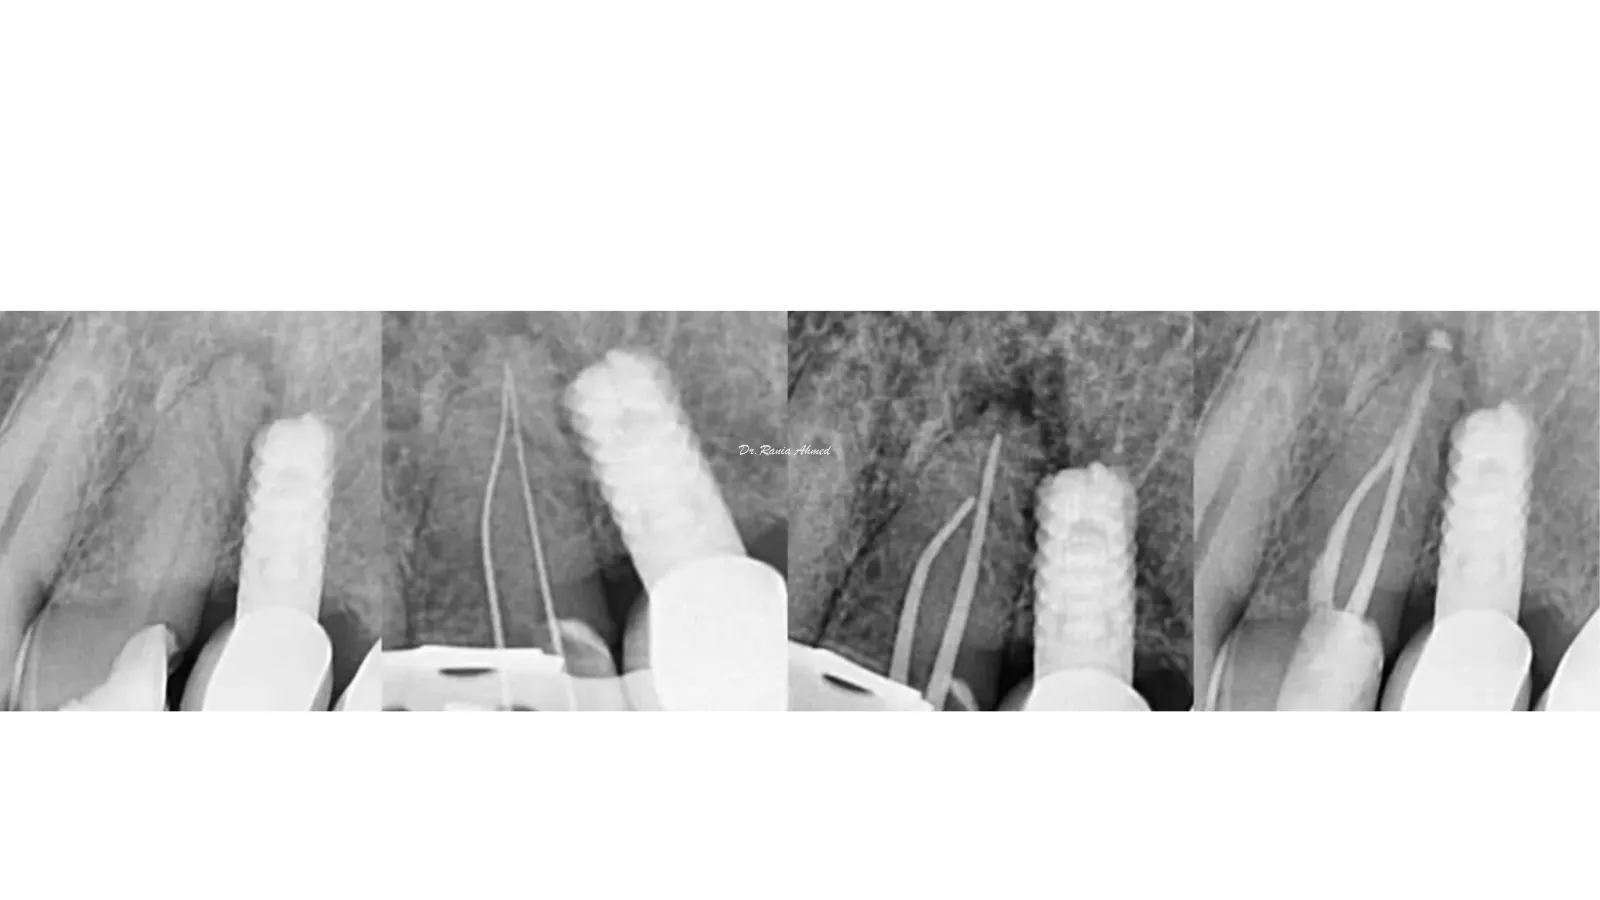

Endodontic Treatment